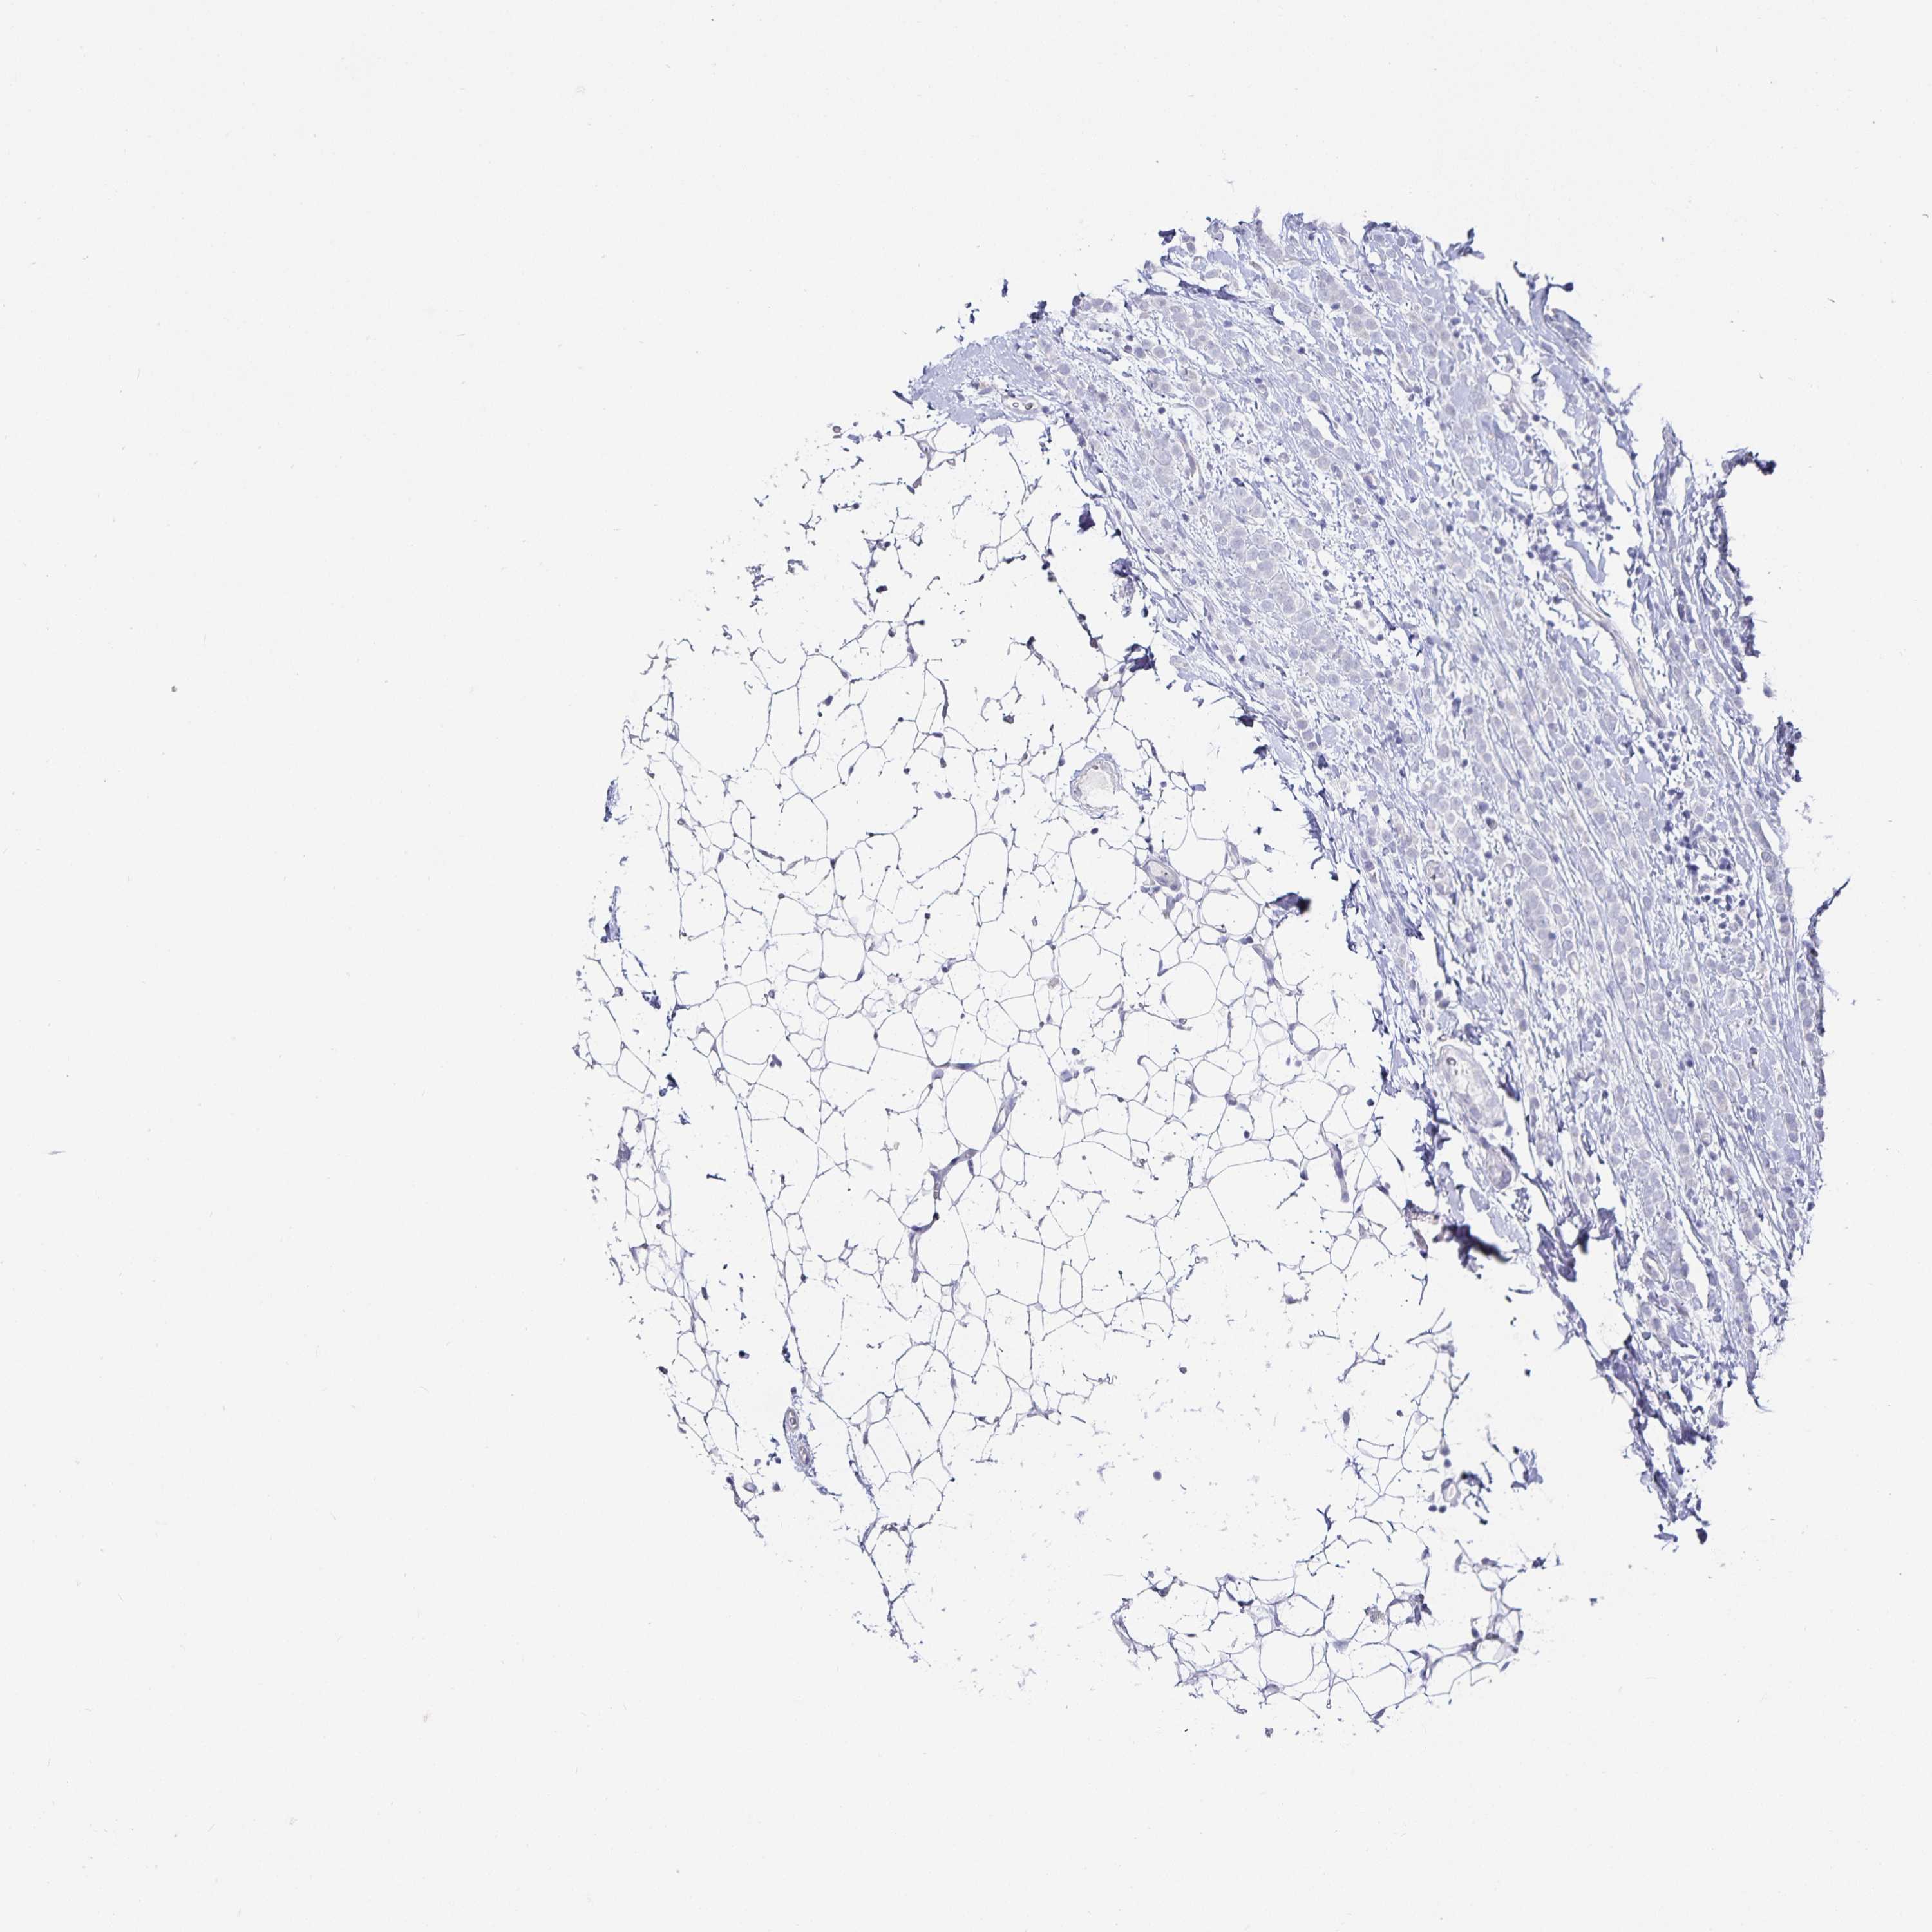

BRCA TCGA BRCA VALIDATION PROTEIN EXPRESSION

ANTIBODIES

AND

VALIDATION